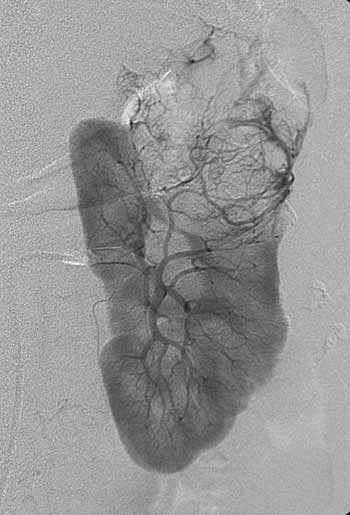

Рис. 1. Рак левой почки. T3a N0 M0. Cеть разнокалиберных опухолевых сосудов, напоминающих языки пламени. Опухоль выходит за пределы контура почки. Внутренняя структура опухоли неоднородная.